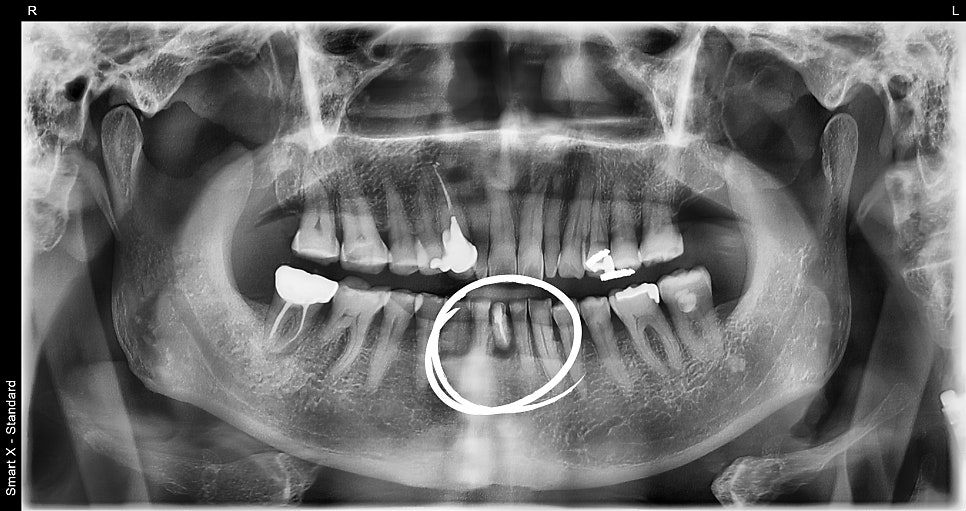

Initial X-ray taken at the first visit

The patient visited the clinic with the chief complaint that the lower front tooth was severely loose,

and the panoramic X-ray showed that preserving the natural tooth was not possible.